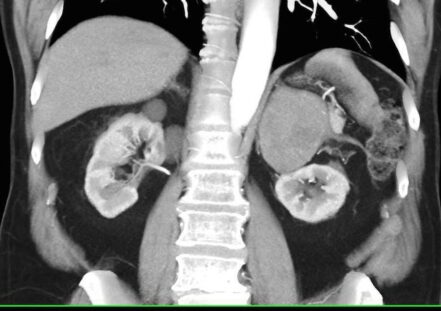

TC DE GLANDULAS SUPRARRENALES.

La hemorragia suprarrenal es una entidad infrecuente que puede ser uní o bilateral.

Cuando es unilateral suele ser clínicamente silente y en la mayor parte de los casos se diagnostica de forma incidental.

Sin embargo, la hemorragia bilateral por lo general desencadena una insuficiencia suprarrenal aguda, a veces dando como resultado el coma o la muerte si la terapia de reemplazo de esteroides no se administra con prontitud.

Las causas de hemorragia suprarrenal se dividen en traumáticas (la mayoría unilaterales y derechas) y espontaneas, agudas y crónicas.